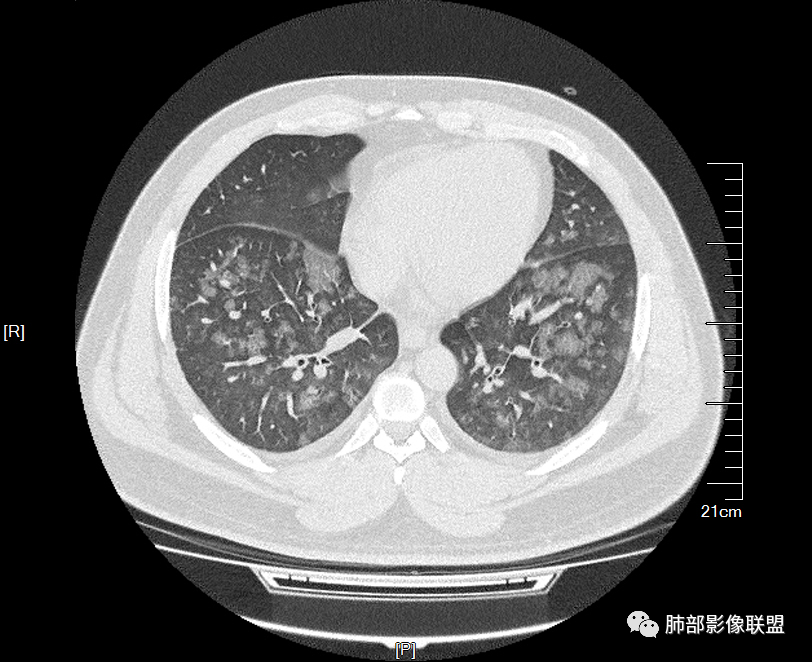

双肺多发腺泡结节及磨玻璃,小叶间隔增厚(大网格状),腺泡结节内及磨玻璃内可见细网格影(小叶内间隔增厚),影像表现符合肺泡出血改变,血肌酐升高,考虑肺肾综合征。鉴别肺水肿。

双肺多发腺泡结节及斑片状磨玻璃影,边缘不清,后者内见细网格状改变,小叶间隔增厚,呼吸系统症状不明显,考虑肺水肿,过敏性肺泡炎代排

32岁男性,左足痛入院。有痛风、肌酐升高、高血压病史。CT:两肺弥漫磨玻璃结节,小叶间隔增厚、小叶内间质增厚,两侧少量胸水。考虑:1.肺水肿;2.过敏性肺炎;3.肿瘤?

双肺多发腺泡结节及磨玻璃网格影,部分融合,小叶间隔增厚,双肺中轴间质增厚不明显,疾病谱:病毒性肺炎,肺泡出血,水肿,过敏性,肺泡蛋白沉着症,PCP。结合病史,没有咳血,肺泡出血,不考虑,过敏没有任何临床症状,而且无上肺分布优势,也排除。病毒性肺炎也无临床支持,排除。PAP影像不典型,暂排除。有肾功能异常,所以考虑1肾源性肺水肿。2,有无激素使用史或HIV,PCP待排。

青年男性,双肺多发大小不等斑片状磨玻璃密度影,内见细网格影,并可见小叶间隔增厚,双侧胸腔少量积液,患者曾有血肌酐增高,提示曾有肾损害,并有痛风、高血压病史,考虑肺肾综合征,鉴别过敏性肺炎

多发GGO结节,边界清,以全小叶、小叶中心为主:

GGO背景

小叶间隔增厚,无明显重力趋势

细网格也明显

中轴间质增厚,小叶间隔增厚,小叶内间质增厚,部分重力作用,双侧对称,胸水,按理淋巴道回流受阻有

肺水肿类病变有

问题是腺泡结节如何解释?

1.间质性肺水肿 :小叶间隔增厚,尚光滑,支气管血管束增粗,胸膜或叶间裂增厚,肺内有磨玻璃密度影,有重力分布趋势。

2.肺泡性肺水肿 :

(1)中央型分布:以肺门为中心,两肺中内带对称分布的大片状实变,称为“蝶翼征”。常见于心源性及肾源性肺水肿患者。也可表现为磨玻璃密度病灶,弥漫性分布或以小叶中心性分布。

(2)弥漫型肺水肿:弥漫分布于两肺内的多发斑片状磨玻璃密度及实变影,大小和密度不等,可融合成大片状阴影,可见空气支气管征。